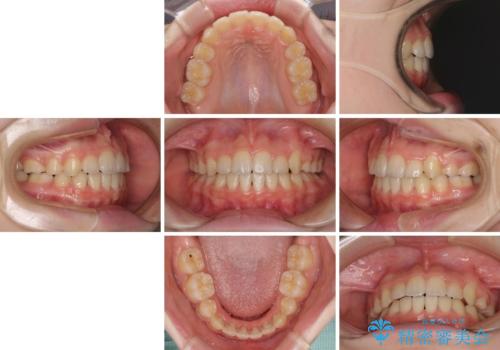

乳歯が残っている 目立たない装置での抜歯矯正

- 八重歯と乳歯が残っていることを気にして来院された患者様です。

乳歯が3歯残っており、下顎は左右ともに後続永久歯がない状態でした。

口元が突出しており、口が閉じにくかったため、乳歯を含め上下5歯を抜歯して矯正治療を行うこととしました。